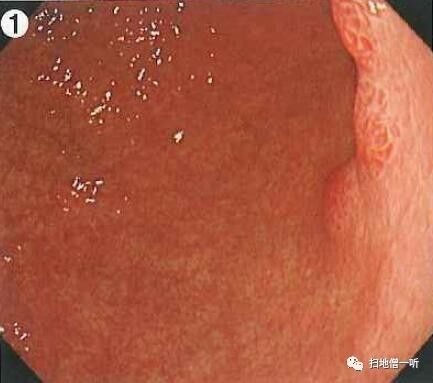

A2:息肉样病变在图3及图4

体上部大弯前壁可见发红息肉样隆起性病变,周围粘液较多,冲洗干净后需考虑与增生性息肉?胃癌?等鉴别。